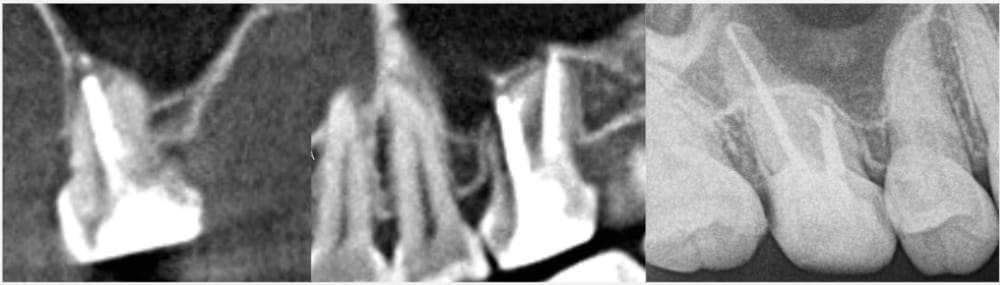

右上6番は、近心根管のパーフォレーション(穿孔)が疑われ、そこから根尖孔外へレントゲン的に白く写る不透過性物質の押し出しが確認できました。性状から、貼薬材料あるいは根管充填に使用するシーラーであると推測されました。

CT画像による三次元的比較

CT画像上でも、根尖部の骨の回復と漏出していた材料の消失が認められます。